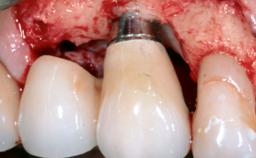

Despite anti-infective surgical treatment, some patients may experience recurrent infection and progressive bone loss requiring additional treatment. This case describes a conservative approach using an implant retrieval tool without the need for excessive bone removal or use of a trephine.

A 65-year-old female patient was referred to the periodontist for assessment and management of infection associated with an implant at site 12. The general dentist had noted suppuration on probing during examination.